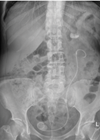

Nephrocalcinosis

Case 1 What does this x-ray of the kidney, ureter and bladder (KUB) show? What are the likely causes? What is the pathology behind medullary sponge kidneys (MSK)? What is the risk of urolithiasis with MSK? How are such patients...